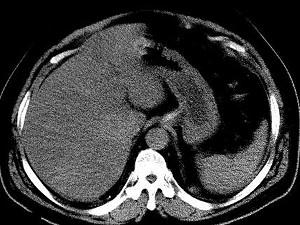

问题 男,32岁,肥胖,常酗酒,肝肋下一横指,肝区轻微压痛,影像表现如图,应诊断为 ( )

选项 A、肝豆状核变性 B、肝含铁血黄素沉着 C、肝硬化 D、脂肪肝 E、肝炎

答案 D